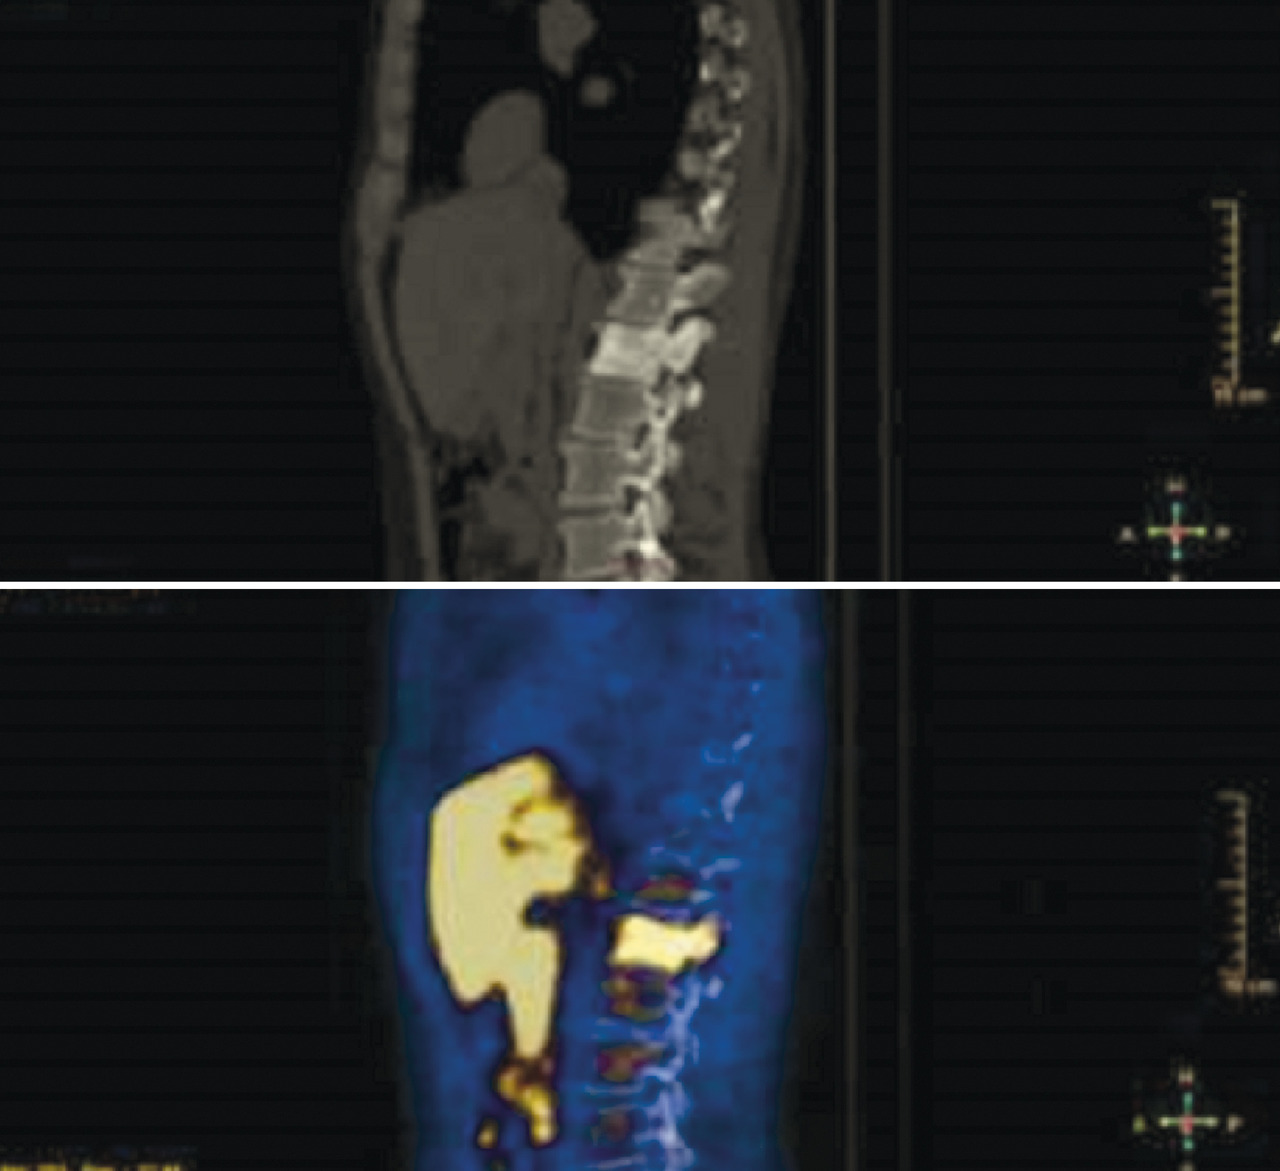

Plus récemment, d’autres méthodes d’imagerie ont permis d’améliorer la précision du bilan d’extension, notamment la tomographie par émission de positons (TEP), avec différents traceurs. La TEP est un examen d’imagerie fonctionnelle qui permet de mesurer en trois dimensions l’activité métabolique des tissus. Elle est couplée à un scanner classique, qui permet de préciser les zones d’hypermétabolisme par superposition des deux iconographies. La TEP repose sur le principe général de la scintigraphie, qui consiste à obtenir des images après l’injection d’un « traceur » faiblement radioactif : pour l’étude des cancers de prostate, le plus largement utilisé est le [18F]fluorocholine (

De multiples paramètres cliniques et anatomopathologiques peuvent contribuer au bilan d’extension de la maladie, en particulier s’ils sont insérés dans des nomogrammes spécifiques ou via des modèles prédictifs. Il faut aussi souligner que l’exécution des examens d’imagerie doit être recommandée en fonction de la classe de risque spécifique de chaque patient, selon la nécessité d’avoir un bilan plus précis, qui peut modifier la procédure thérapeutique (

Un bilan d’extension correct, c’est-à-dire une définition précise de l’étendue de la maladie via des examens d’imagerie appropriés, représente le point de départ pour établir la meilleure stratégie thérapeutique, obtenir des informations sur le pronostic et comparer les résultats des différentes options thérapeutiques.